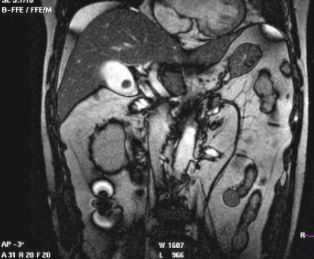

膽結(jié)石癥是膽道系統(tǒng)的常見病變,發(fā)病率為8%以上。按化學(xué)成分可將膽石分為3種類型:膽固醇類結(jié)石,膽固醇含量占80%以上;膽色素類結(jié)石,膽固醇含量少于25%;混合類結(jié)石,膽固醇含量占55%~70%。在我國以膽色素結(jié)石為主。 膽囊結(jié)石的CT表現(xiàn): CT的密度分辨率高,更有利于膽結(jié)石的發(fā)現(xiàn)。膽石的CT表現(xiàn)與其化學(xué)成分密切相關(guān),其CT值與膽固醇含量呈負(fù)相關(guān),與膽紅素和鈣含量呈正相關(guān)。

CT表現(xiàn)主要有:高密度結(jié)石(均勻或不均勻);略高密度結(jié)石;等密度結(jié)石,與膽汁密度相等平掃不易區(qū)分;低密度結(jié)石;環(huán)狀結(jié)石。